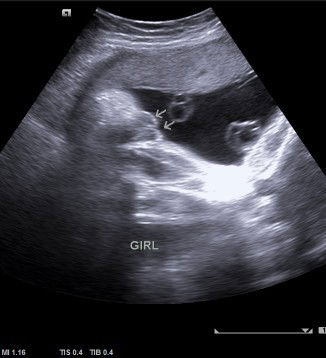

Hai mommy semua. .saya mula² scan baby 19 week dan 25 week doktor ckp baby boy. .dan saya scan semula 30 week doktor ckp baby girl pulak. .apa pendapat mommy semua bila lihat gambar scan yang saya share ni. .